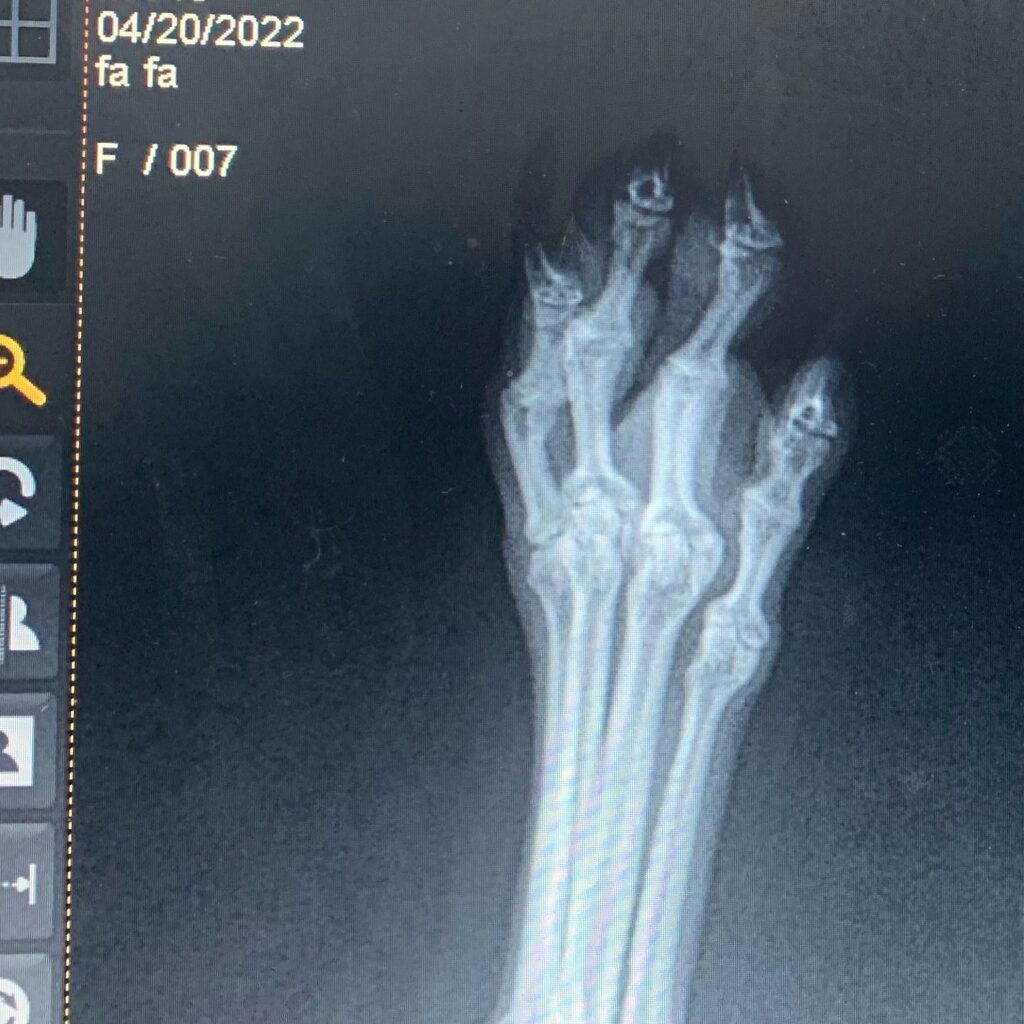

1. 花花已睇醫生照x-ray,可幸冇傷到骨,但腳指頭有肉壞死,要每日觀察住,希望唔會惡化

2. 最壞最壞嘅情況,如果真係惡化,嗰一部份壞死組織要切除😭,拜託大家祝福我女早日康復唔會惡化🙏🏻🙏🏻🙏🏻 [編按:以下有血腥圖片,自行斟酌睇唔睇落去]